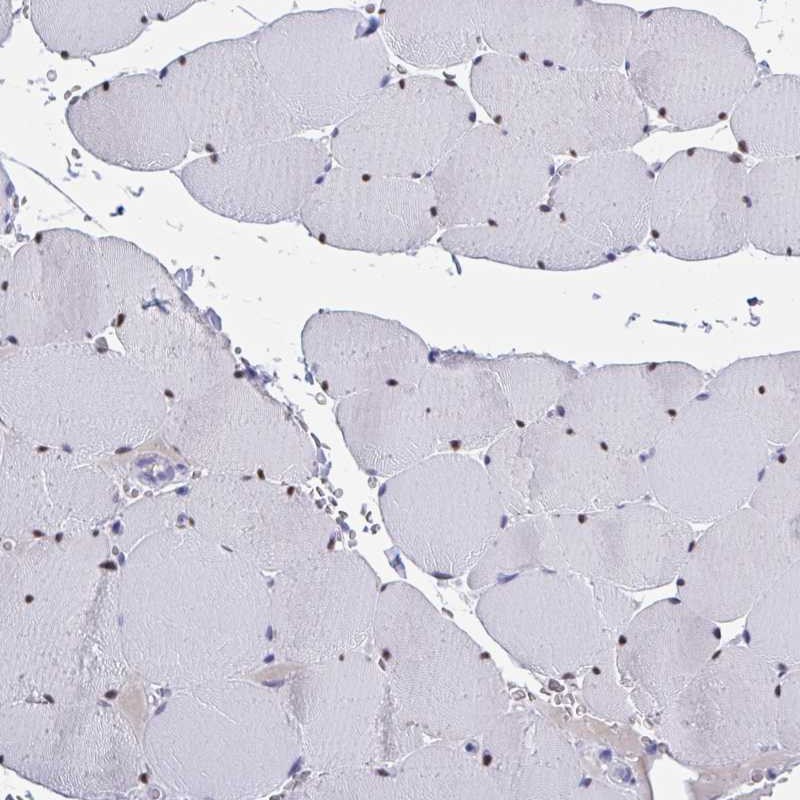

Immunohistochemical staining of human skeletal muscle shows strong nuclear positivity in myocytes.